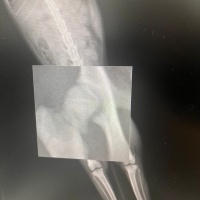

Merhabalar, sekiz aylık kedimin yüksekten düşme sebebiyle sağ arka bacagı kırıldı. Veterinerimiz bir haftalık kafes istirahati ve kalsiyum takviyesi ile kayanayabilecegini söyledi. Hem genç oldugu için hemde kırık çok ayrılmadıgı için. Kalsiyum kaici kedi yogurdu, vitamin malt, kemik iliği suyuyla destekliyorum. Ödül mamalarını falan reddetmiyor mamasını da yiyor ama suyun yüzüne bile bakmıyor. Kaşıkla diline bırakıyorum öyle içiyor. Başına gelen var mı bilmiyorum ama hem kırıkla ilgili yorum hemde su konusunda tavsiyesi olan var mıdır? Fotograf ekliyorum